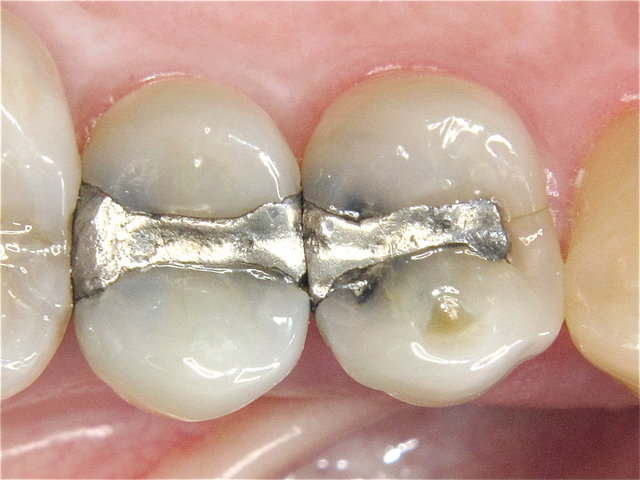

Randspalten in undichter Amalgam-Füllung ...

Composit-Füllung by CLINICDENT ✓